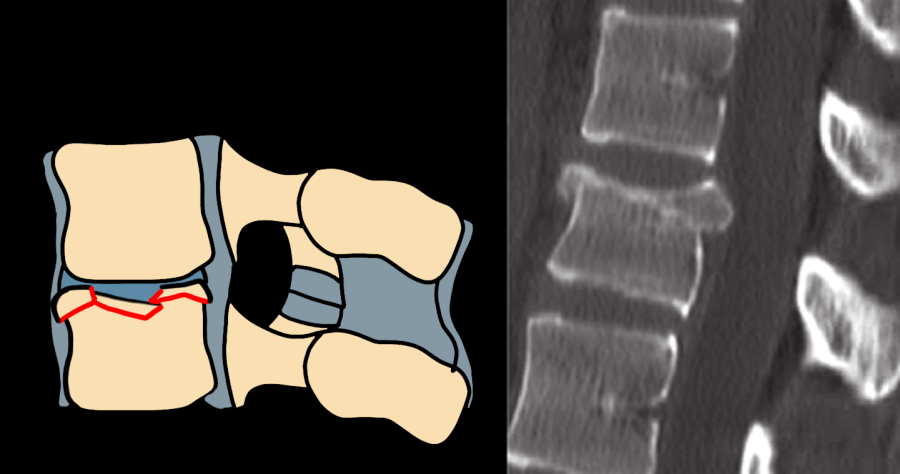

AO Type B1/B2 flexion-distraction Chance fracture — diagram and CT showing posterior tension band disruption with anterior distraction

Type B1/B2 — flexion-distraction (Chance fracture equivalent); posterior tension band failure